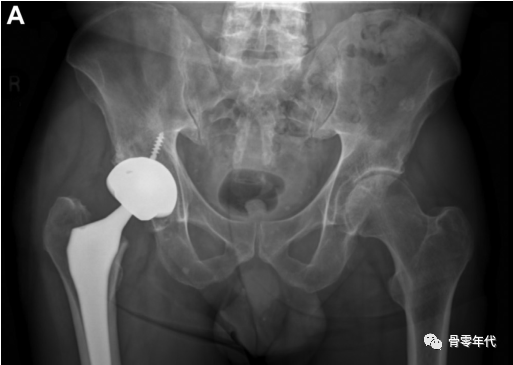

通过比较术前(A)和术后(B)骨盆的放大校正X线片,评估LL(#)、GO(+)和FO(*)的变化.